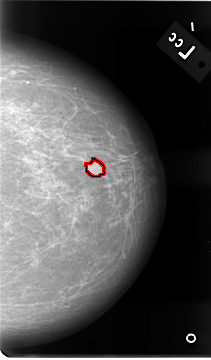

B_3086_1.RIGHT_MLO

FILE: B_3086_1.LEFT_MLO.OVERLAY

TOTAL_ABNORMALITIES 1

ABNORMALITY 1

LESION_TYPE MASS SHAPE OVAL MARGINS OBSCURED-ILL_DEFINED

ASSESSMENT 3

SUBTLETY 2

PATHOLOGY MALIGNANT

TOTAL_OUTLINES 1

BOUNDARY